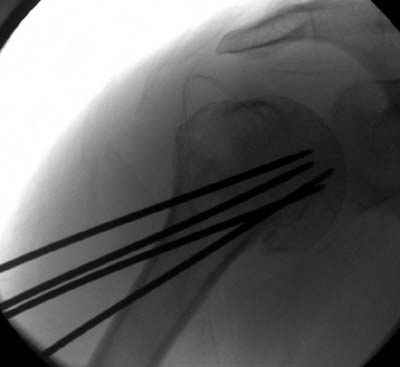

Здравствуй Женя. Во первых спицы, вводимые в головку плеча ретроградно, никогда не имели V-образную форму, если говорить о методике моей операции ЦИТО. Чтобы легче было запомнить Y-образную форму, вспомни крепление новогодних елочных шаров - очень демонстративно. Кроме того если ты внимательно посмотришь, то увидишь, что вся конструкция имеет некоторую кривизну по плокскости, величину, которой ты можешь задать сам. Сначала мы проводим проксимальный пучок, а в момент пересечения линии перелома мы

ротируем спицу таким образом, чтобы дистальный изгиб прямо противодействовал смещающим силам - поврот за ушко под контролем ЭОПа. Дистальный пучок стараемся провести так, чтобы его бранши расклинились и прошли по обе стороны предыдущего пучка, что создает дополнительное напряжение на

протяжении контакта. Для оценки правильности проведения спиц очень важно, чтобы ЭОП стоял строго перпендикулярно плоскости сустава, в противном случае - в рентгене есть эффект отбрасывания тени - прохождение косого луча дает удлиненное изображение спиыц и создается впечатление, что спица стоит уже в субхондральном слое. На первых операциях у нас было довольно частое несовпадение длины контрольной спицы и мы провизорно добавляли от 0,5 до 1,0 см уже на фиксирующем пучке. Входные отверстия лучше располагать по наружной и передней поверхности плеча на расстоянии не менее 2-х диаметров головки.

Такой выбор входных отверстий обусловлен прямой возможностью попадания в малый и большой бугорки за счет изгиба спиц по длине и отражения из от внутреннего кортикала проксимальнее точки введения. Поскольку анатомически бугорки не составляют артикулирующую поверхность, то некоторое выстояние спиц только усилит стабильность. Входное отверстие мы используем 6 мм в диаметре, для эффективного раскрытия петли-пружины. Спицы перед проведением

проверяем на достаточную эластичность и упругоустойчивость, мягкие спицы отбраковываем. В данном примере создалось впечатление, что одна бранша V-спицы скользнула по картикалу снаружи? Все это безболезненно можно переделать, расширив теже отверстия, изогнув спицы, повернув их в разные стороны и добавив еще пучки Y-ОБРАЗНЫХ, а не V-образных (эти пучки выталкивает, особенно если они прямые - пружина работает в обе стороны).

Что-то, наверно, сделали мы не совсем оптимально, поскольку у Анатолия Федровича и его соратников как-то красивее "раскрываются" спицы в головке плеча - надеюсь, он прокомментирует и подскажет, что надо подправить.